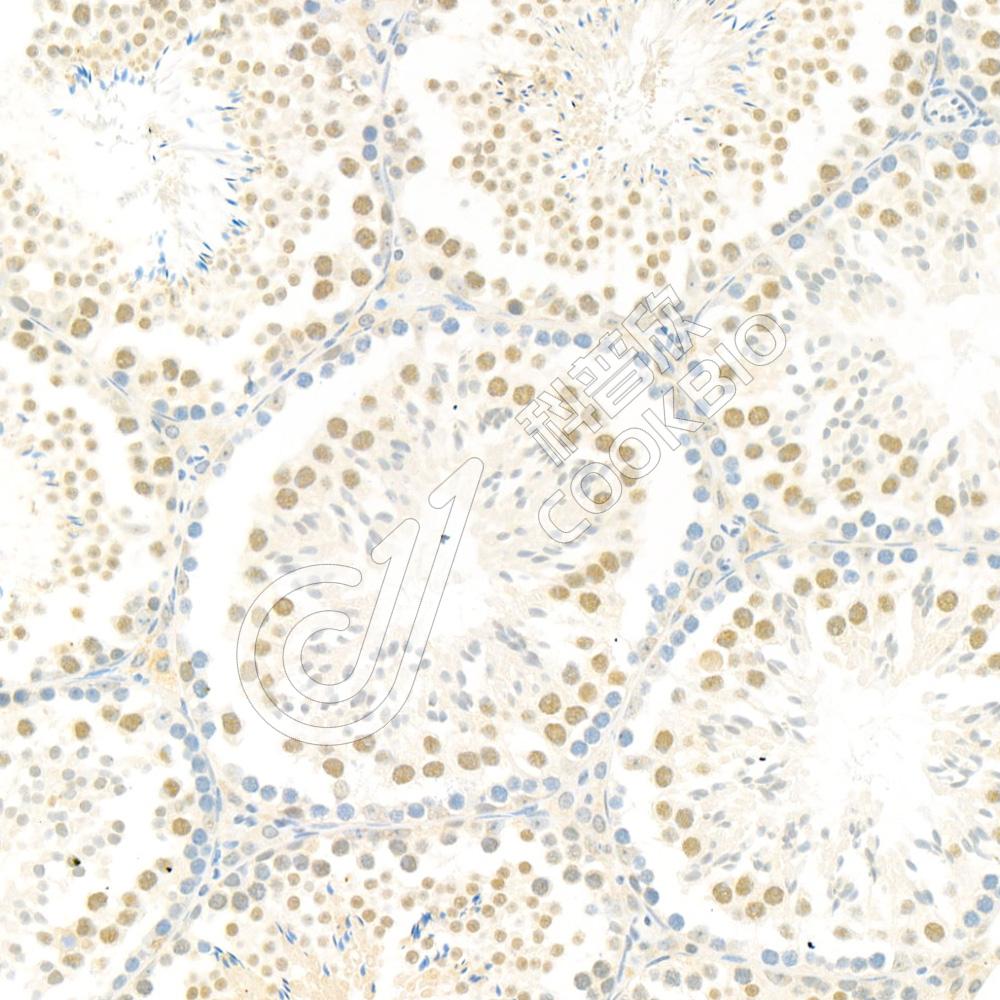

IHC检测Bub1蛋白(货号 K1333693).

样品: 小鼠睾丸, 4%多聚甲醛 (货号KSG1101) 固定12-24小时.

抗原修复: 柠檬酸抗原修复液(干粉, pH 6.0) (KSG1201), 98℃, 20分钟.

—抗: 1: 1200稀释, 4℃ 孵育过夜.

二抗: S-vision免疫组化多聚二抗(山羊抗兔),即用型 (货号KB3906), 室温孵育20分钟.